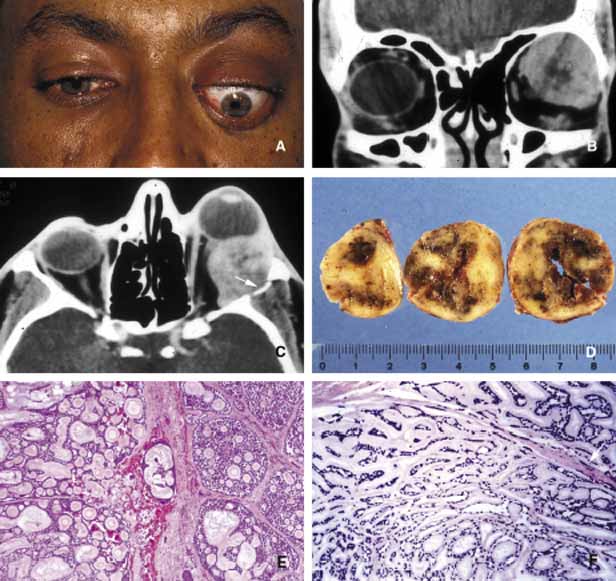

Fig. 14 Benign mixed tumor (BMT). Coronal CT (A) depicts a well-delineated mass in the superior lateral orbit causing inferior medial dislocation of the globe. Frame B shows multilobulated nature of pleomorphic ademona (benign mixed tumor). The tumor nodules are bisected to show the encapsulation and the focal nature of the tumor masses; the nodule on the right was discovered inferior to the main lesion as a satellite mass (B). Histopathologically pleomorphic adenoma is composed of a mixture of glandular (g) and myxoid (m) tissues (C, D). Some of the glandular formations may develop squamous metaplasia and distend to form cystic space (c) secondary to keratin accumulation. (D)

Fig. 15 Adenoid cystic carcinoma. A large superior temporal mass causing marked proptosis of the eye and inferior displacement (A, B, C). The axial CT scan depicts the infiltration of the lateral wall with the tumor (arrow) (C). Serial sectioning of the tumor showing focal areas of hemorrhagic necrosis and cystic changes (D). Frames E and F depict the histopathological appearance of adenoid cystic carcinoma forming a “Swiss cheese” pattern with proliferation of atypical, irregular, glandular structures. Peripheral nerve sheath involvement (arrow) is seen in frame F.